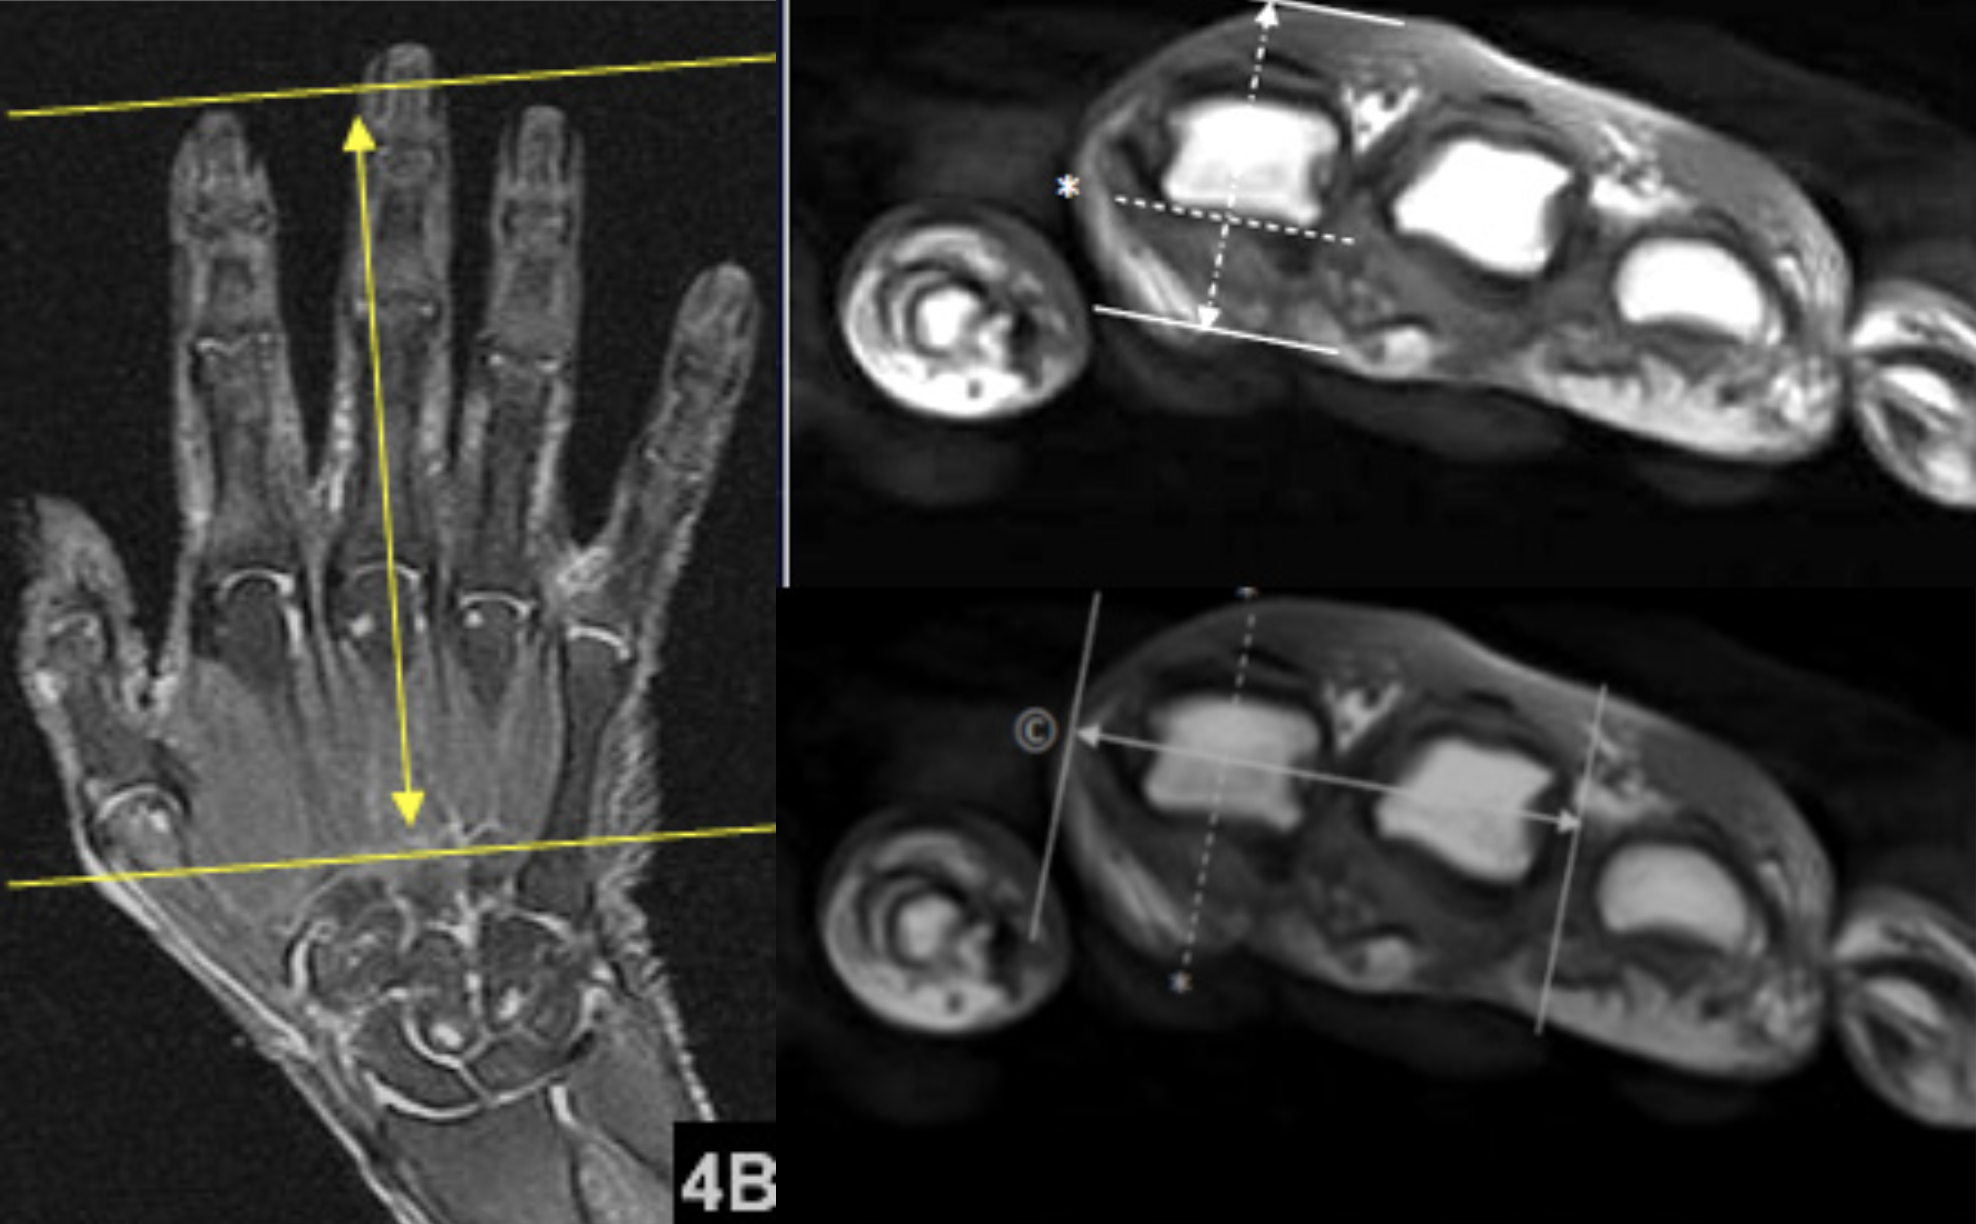

| AXIAL | Mid TE (40-50) T2 Fat Sat | TSE | 2mm | 0.3mm | SPAIR | 12cm | Cover MCP Joints thru DIP Joints |

| COR | T1 | TSE | 2mm | 0.3mm | None | 12cm | Angle Relative to MCP Joint |

| COR | Mid TE (40-50) T2 Fat Sat | TSE | 2mm | 0.3mm | SPAIR | 12cm | Angle Relative to MCP Joint |